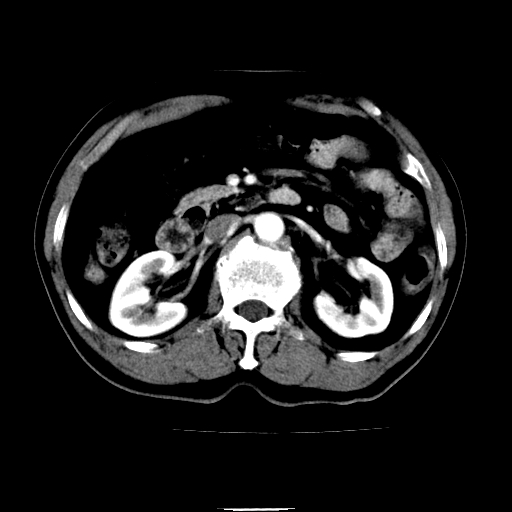

以下是引用chenqiong在2010-3-25 20:56:00的发言:[br]1、胆囊炎,胆囊息肉[br]2、肝内胆管及胆总管扩张,胆总管下端结石[br]3、十二指肠乳头旁憩室

以下是引用zxl51642在2010-3-26 10:47:00的发言:[br]胆囊炎,胆囊息肉,胆总管扩张,但未看到明显肿块,肝内胆管扩张不像恶性,炎性狭窄或阴性结石可能吧,建议mrcp,右肾小囊肿